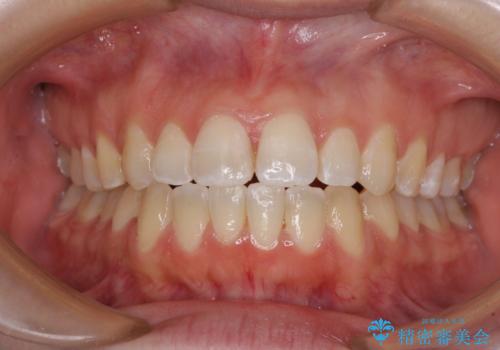

【モニター】オープンバイトをインビザラインで矯正治療

- 前歯の上下スペースによる食べにくさを気にして来院された患者様です。

インビザラインにより上下の前歯の隙間を閉じていくこととしました。

前歯のデコボコの解消と並行して上下の奥歯を圧下させるようにすることで、前歯を接触させるように計画しました。

上下の隙間に舌が入り込むことがオープンバイトの原因であったため、舌の筋肉のトレーニングも並行して行い、後戻りの抑制を図りました。